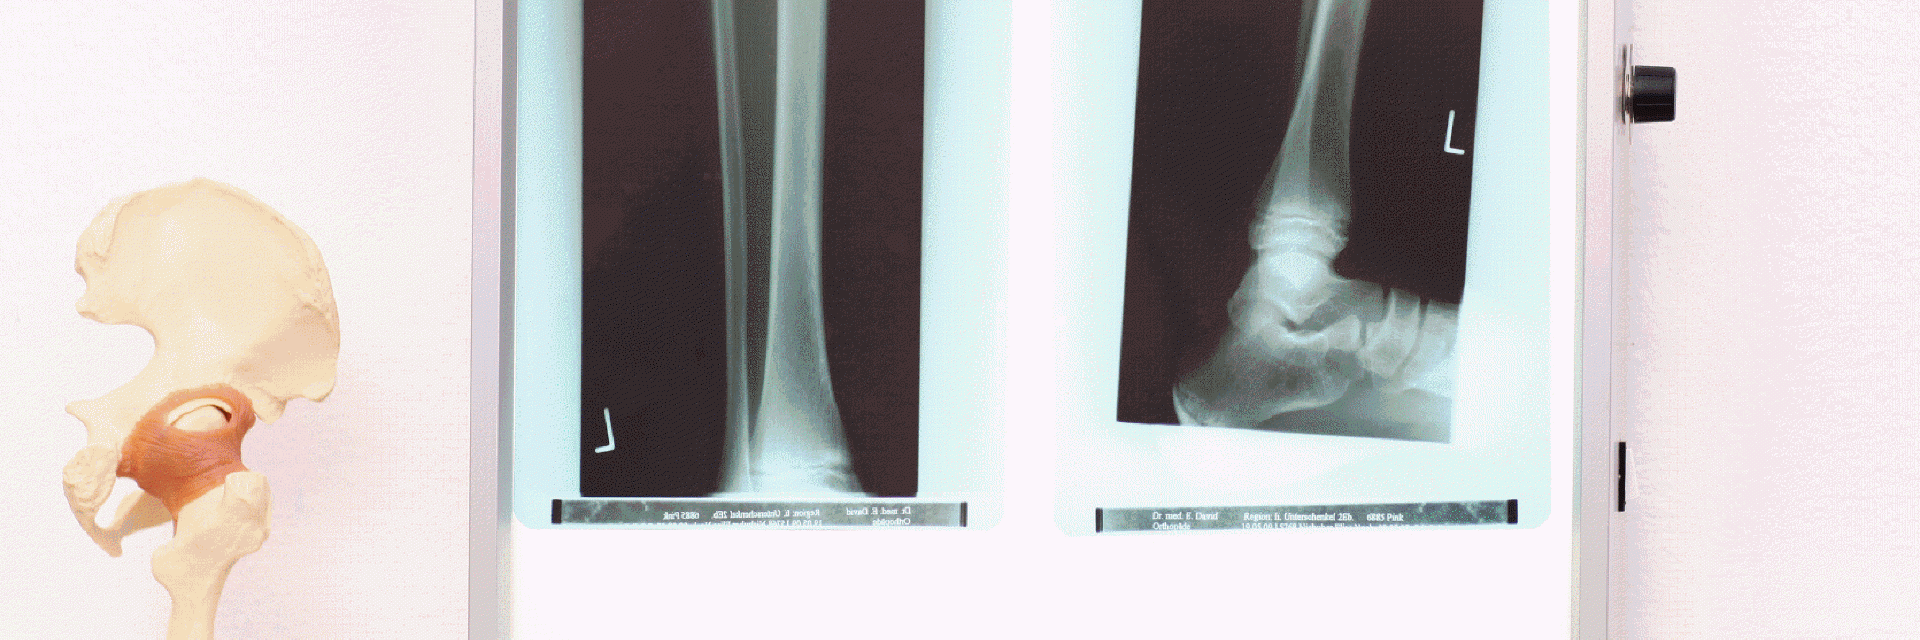

Sprunggelenk - Fuß

OP – Verfahren: Sprunggelenk und Fuß

Eine wachsende Zahl Erwachsener, Jugendlicher und Kinder leidet an Fuß- und Sprunggelenksbeschwerden. Die Beschwerden können

bei angeborenen Fehlstellungen auftreten, durch das Schuhwerk oder durch Unfallfolgen bedingt sein.

Die häufigsten Erkrankungen sind:

Arthrose im oberen Sprunggelenk

Abhängig vom Erkrankungsbild, Ausmaß und Lokalisation der Beschwerden können offen– chirurgische oder arthroskopische Operationstechniken angewendet werden. Einige der Eingriffe können auch ambulant durchgeführt werden.